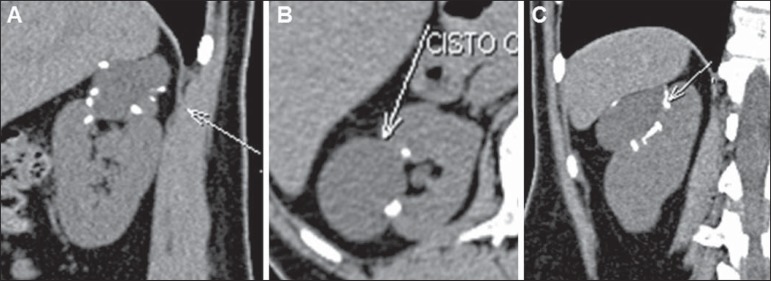

Figure 4.

Bosniak category IIF. MDCT, coronal (A), axial (B) and sagittal (C) reconstructions demonstrating the presence of a right renal cystic lesion with parietal thickening (arrow on B) and a thin septum (arrow on C). Minimally complicated cyst requiring follow-up.

Figure 5.

Bosniak category IIF. MDCT images, sagittal (A), axial (B) and coronal (C) reconstructions demonstrating the presence of a cystic lesion in the right kidney, with nodular, parietal calcifications. Minimally complicated cyst requiring follow-up.

These lesions may present with thick nodular calcifications (Figure 5) and irregular contours, increasing in volume with time, without indicating malignancy(12,13,22,23,25). Israel et al.(12) have demonstrated that all the lesions classified as category IIF presented calcifications, but also had their greatest concentrations. In some cases, because of the high number of such calcifications, the visualization of contrast enhancement may be difficult, so the use of images subtraction is suggested for differentiation between categories IIF and III(12). Unfortunately, septations and wall thickening cannot be quantified to change a cyst category from II to IIF(22).